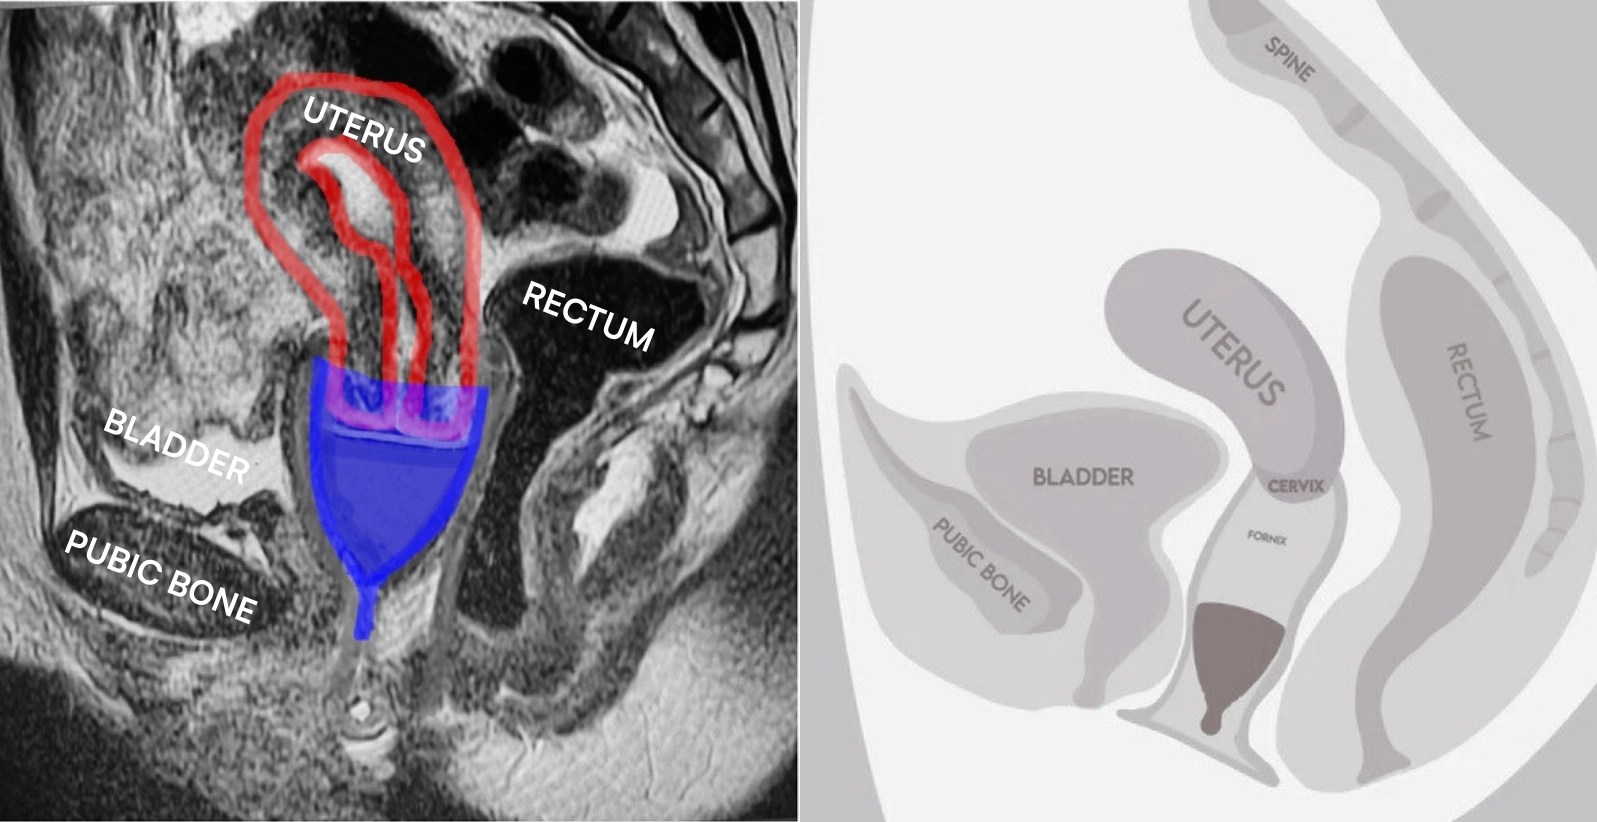

Oraz głębiej, niż pokazuje większość ilustracji producentów. Podczas gdy wiele rysunków instruktażowych przedstawia kubeczki menstruacyjne bardzo nisko w pochwie, obrazowanie rezonansem magnetycznym (MRI) w realnym życiu jednoznacznie wskazuje, że prawidłowo założony kubeczek menstruacyjny znajduje się wysoko w pochwie, z obręczą obejmującą szyjkę macicy, a kanał pochwy ściska się poniżej kubeczka, uszczelniając go wewnątrz ciała.

Po lewej rezonans magnetyczny (MRI) pokazujący założony kubeczek menstruacyjny. Kubeczek na niebiesko, macica na czerwono. Szyjka macicy znajduje się wewnątrz kubeczka. Po prawej przykład rysunku instruktażowego ze strony producenta kubeczków menstruacyjnych (źródło: hello period). Pochwa jest najwęższa w przedsionku, wyżej się rozszerza, zbyt niskie umiejscowienie kubeczka menstruacyjnego (jak na rysunku po prawej) uniemożliwi jego pełne otwarcie i uszczelnienie.

Włóż kubeczek menstruacyjny za przedsionek pochwy, aż jego góra trafi nad kością łonową (twarde wybrzuszenie na przedniej ścianie pochwy). Pochwa jest najwęższa w przedsionku, wyżej się rozszerza. Głębsze umiejscowienie kubeczka menstruacyjnego ułatwi jego pełne rozłożenie.

Prawidłowo założony kubeczek znajduje się wysoko w pochwie, pod szyjką macicy. Ściany pochwy poniżej naturalnie się zamykają, uszczelniając go. Górna krawędź kubeczka zazwyczaj mieści się powyżej kości łonowej, w sklepieniu pochwy (końcowej części pochwy). Łodyżka powinna być całkowicie schowana. Jeśli wystaje lub uwiera, możesz ją skrócić – ale dopiero po kilku użyciach, gdy nabierzesz wprawy.